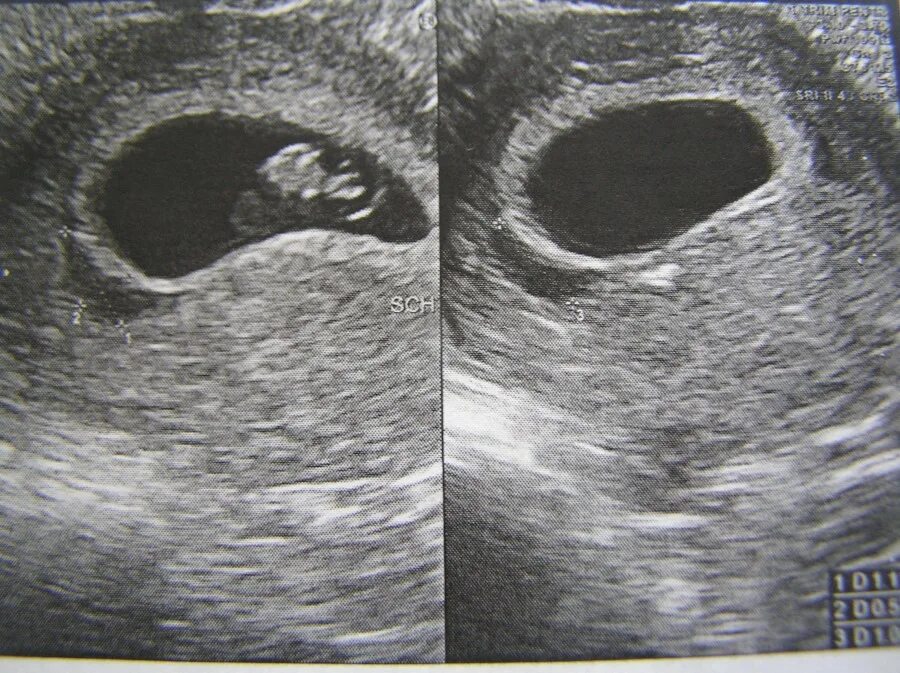

9 недель ощущения